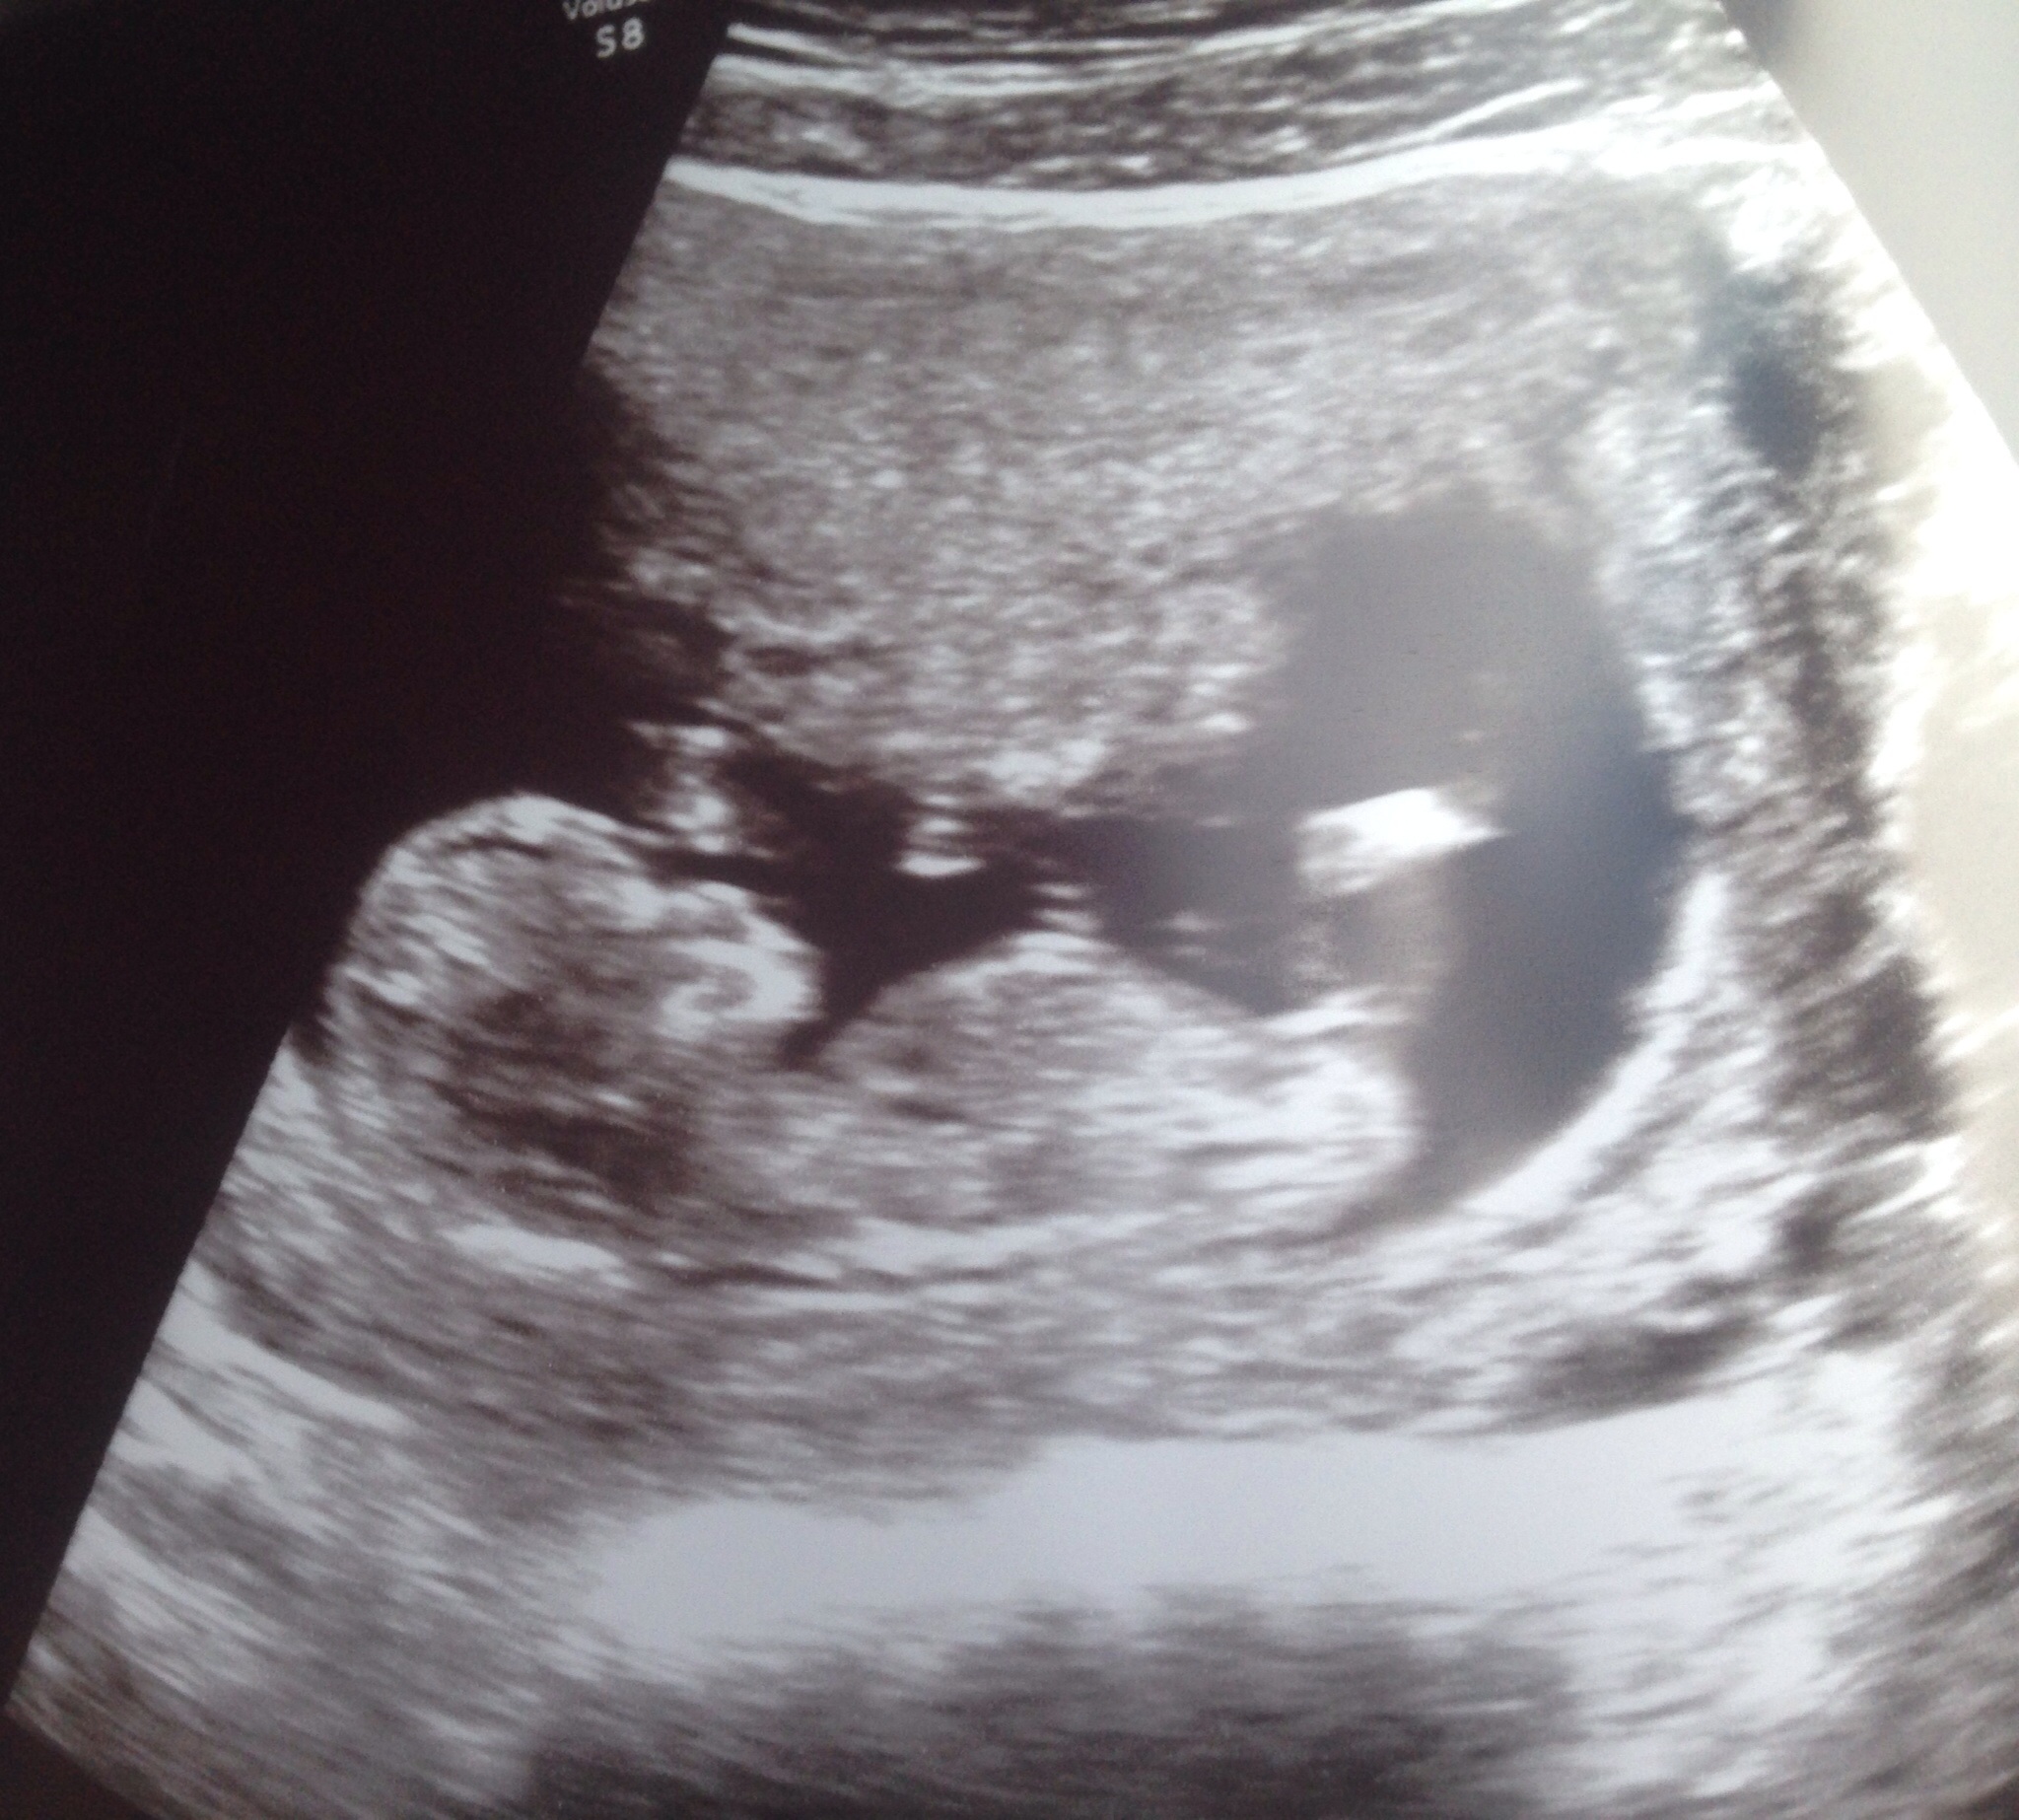

UPDATE: baby is fine and measuring right on track! They scolded me for using a Doppler at all, nevermind that it was "SO early!" I didn't think almost 12wks was that early.. I typically feel kicks around 16wks, when should I use the Doppler then? I guess never according to them. I can see what they're saying but I know after our first loss it helped me immensely early on with my pregnancies so I am definitely greatful to have it! Anyway thank you all for thinking of us today! Here's a couple of pics of our healthy LO